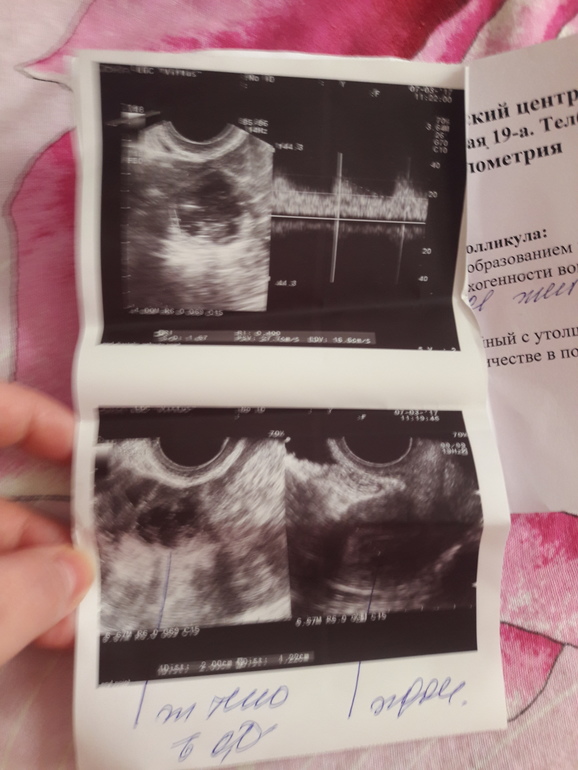

Результаты узи

ФолликулометрияК врачу смогу попасть только на следующей недели. Узи было сделано на 22 дц.

Что значит фолликул с округлым эхонеготивным образованием.......

И эндометрий с утолщенным базальным слоем.